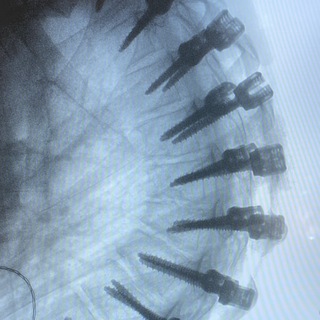

На сагиттальной рентгенограмме женщины, 45 лет: смещен 5 поясничный позвонок кпереди относительно крестца, здесь показана хирургическая фиксация винтами со стержнями и межпозвонковым кейджем.

«Спондилолистез – переднее, заднее или боковое соскальзывание или смещение позвонка относительно нижележащего – можно объяснить элементами дисплазии соединительной ткани. Первое описание спондилолистеза приписывают Herbinaux – бельгийскому акушеру, который отметил костную выпуклость, препятствовавшую родоразрешению. Термин «спондилолистез» был введен Kilian в 1854 г. от spondylos (греч. «позвонок») и olysthesis (греч. «соскальзывание»). Спондилолистез часто формируется на уровне поясничных позвонков, что обусловлено большей статической нагрузкой на них, слабым связочным аппаратом, большой высотой диска, сагиттальной ориентацией суставных поверхностей дугоотростчатых суставов.»

Хитров Н. А. «Возрастные аспекты дорсопатий»

#вертебрология